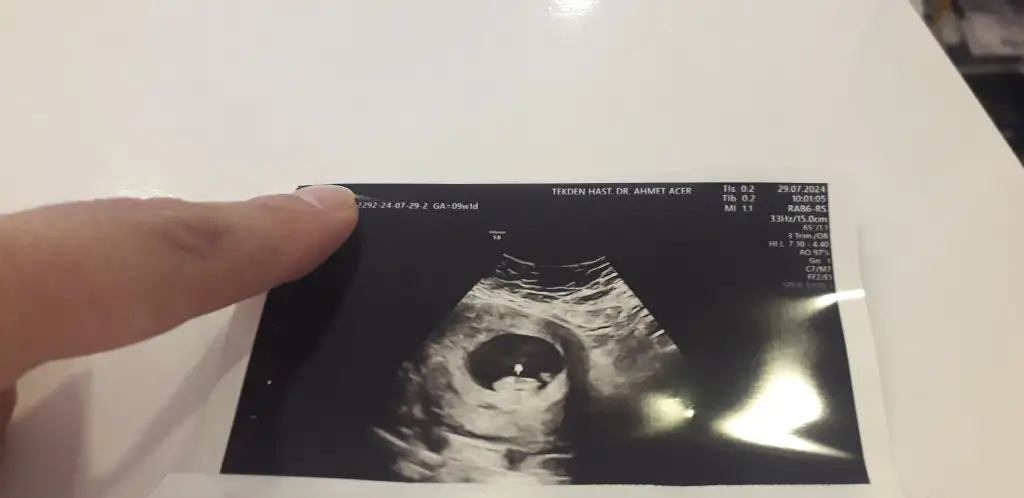

9 hafta 1 günlük cinsiyet tahmini yapar misiniz

• 20240729_124608.webp

20240729_124608.webp

17,4 KB · Görüntüleme: 62

• 20240729_124559.webp

20240729_124559.webp

12,5 KB · Görüntüleme: 64